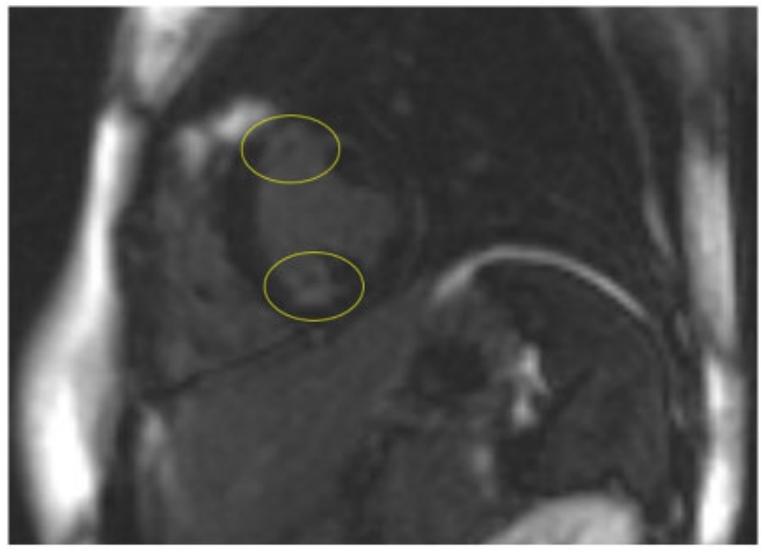

图3 经钆增强的心脏磁共振显示心内膜下纤维化区域(黄色圆圈)病例211